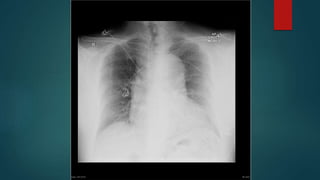

Breathing

Low tidal volumes

Modest fluid

Breathing Low tidal volumes Modestfluid resuscitation Ventilation with Lower Tidal Volumes as Compared with Traditional Tidal Volumes for ALI and the ARDS. N Enlg J Med. 2000; 342:1301-1308. Comparison of Two Fluid-management Strategies in Acute Lung Injury. N Enlg J Med. 2006 Jun;354(24):2564-75. two

• #11 Low tidal volumes has been well established. May have to tolerate a degree of resp acidosis. May need more PEEP also. 861 patients in initial study - no mortality benefit but less time ventilated and in ICU. Later small studies show a 28-day mortality benefit